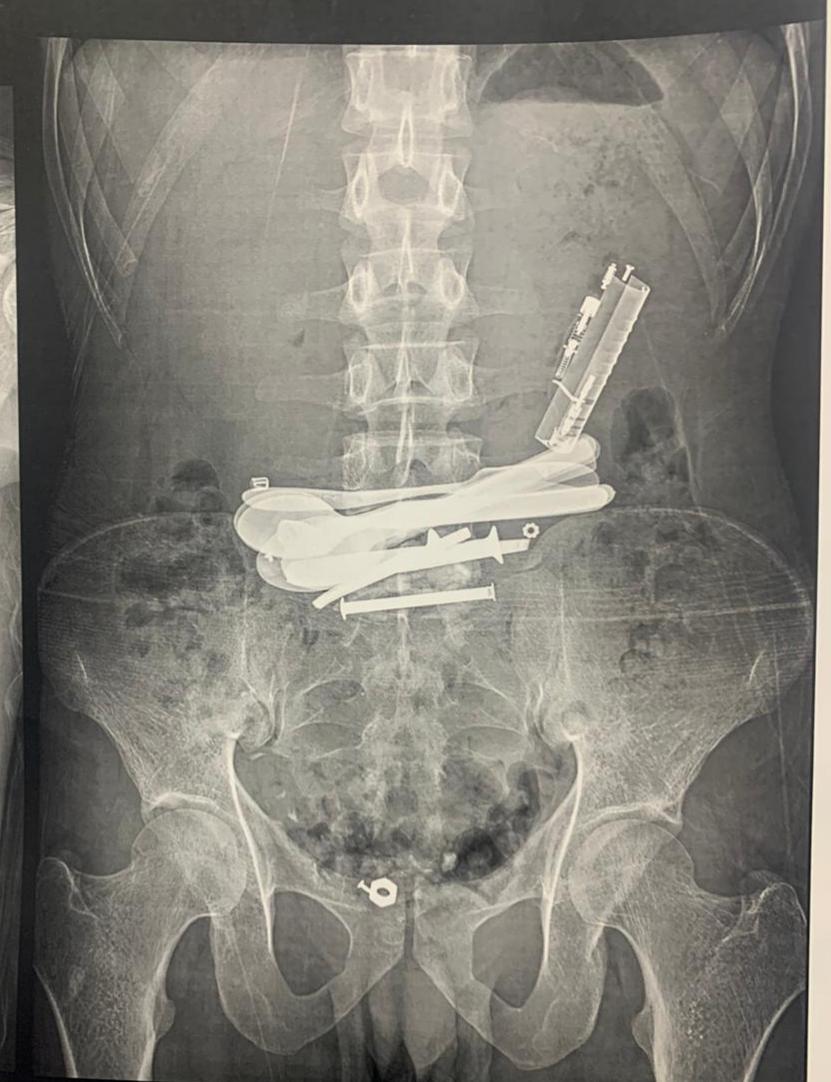

نجح فريق طبى بجامعة بمستشفى سوهاج الجامعى بقسم الجراحة العامة وجراحة الأورام والمناظير في إنقاذ حياة مريض يبلغ من العمر ٣٥ عامًا كان يعاني من آلام حادة بالبطن وقيء مستمر، وبعد الفحوصات تبيّن وجود أجسام غريبة معدنية داخل جهازه الهضمي، نتيجة اضطراب نفسي دفعه لابتلاعها بشكل متكرر.

وأوضح الدكتور أحمد كمال المدير التنفيذي للمستشفيات الجامعية، أن المريض وصل إلى قسم الطوارئ وهو يعاني من أعراض خطيرة، وبعد إجراء الاشعه اللازمه تم اكتشاف وجود معادن حادة مثل ولاعات ومقصات صغيرة داخل الجهاز الهضمي، مما شكّل خطرًا كبيرًا على حياته، الأمر الذي استدعى تدخلًا جراحيًا عاجلًا لتجنب حدوث مضاعفات قد تؤدي إلى ثقب الأمعاء أو انسداد الجهاز الهضمي.

من جانبه أوضح الدكتور علاء السيوطي رئيس قسم الجراحة العامة وجراحات الأورام والمناظير، انه تم التعامل مع الحالة جراحيًا بمنتهى الدقة لاستخراج الأجسام الغريبة بنجاح، مع التأكد من سلامة الجهاز الهضمي وعدم حدوث أي مضاعفات، كما تم عرض المريض على استشاري الأمراض النفسية لوضع خطة علاجية تمنع تكرار مثل هذه الحوادث مستقبلًا، مشيرًا إلى أن المريض خرج من المستشفى بحالة جيدة بعد استكمال فترة المتابعة والعلاج.